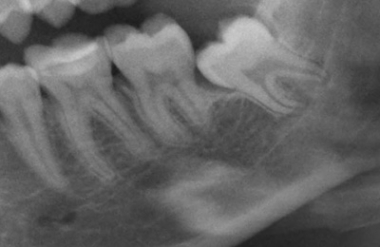

Zahnextraktion und operative Zahnentfernung

Bei einer Zahnextraktion wird der komplette Zahn entfernt. Eine operative Zahnentfernung kann bei brüchigen Zahnwurzeln notwendig werden oder wenn ein Zahnhals zerstört, stark beschädigt, die Zahnwurzel gekrümmt oder abgewinkelt ist oder wenn die gesamte Zahnsubstanz durch Karies stark geschädigt ist. Auch verlagerte, teilweise oder ganz unter dem Zahnfleisch liegende Zähne werden operativ entfernt.

Eine Zahnextraktion, d.h. das Entfernen eines Zahnes, ist ein Routineverfahren, das in den meisten Fällen unter örtlicher Betäubung erfolgen kann. Bei komplizierter Lage des Zahnes, bei Extraktion mehrerer Zähne oder auf Wunsch des Patienten kann der Eingriff auch unter Narkose erfolgen